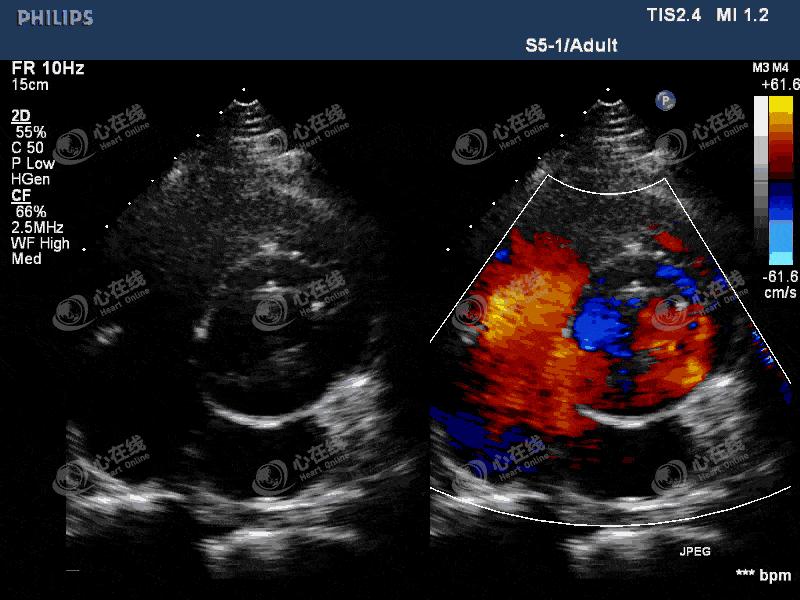

图4 大动脉短轴切面:主动脉瓣机械瓣缝合环外周可见蜂窝状无回声区环绕,机械瓣环活动度增大,机械瓣启闭正常。

图5 彩色多普勒显示,无回声区内可见低速血流穿梭,破口位置位于外科视野7~9点钟位。